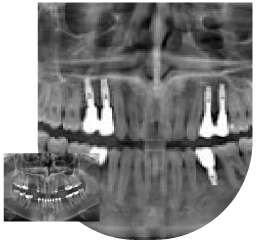

Implantes dentales

Cuando se pierden los dientes, los adyacentes se mueven y se desplazan de su correcta posición, cerrando el espacio e impidiendo su reposición. Con un tratamiento de ortodoncia sencillo, podemos colocar los dientes en su lugar y facilitar la reposición del diente perdido por medio de un implante dentario. Es decir, habría un tratamiento de ortodoncia, previo y posterior al implante del diente o dientes.